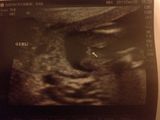

Hi everyone! Happy almost holidays! We had our A/S this week and were told its a girl. I am thrilled BUT cant help to notice something between the legs that doesnt look so girly. Can you take a look and let me know what you think? THANKS!